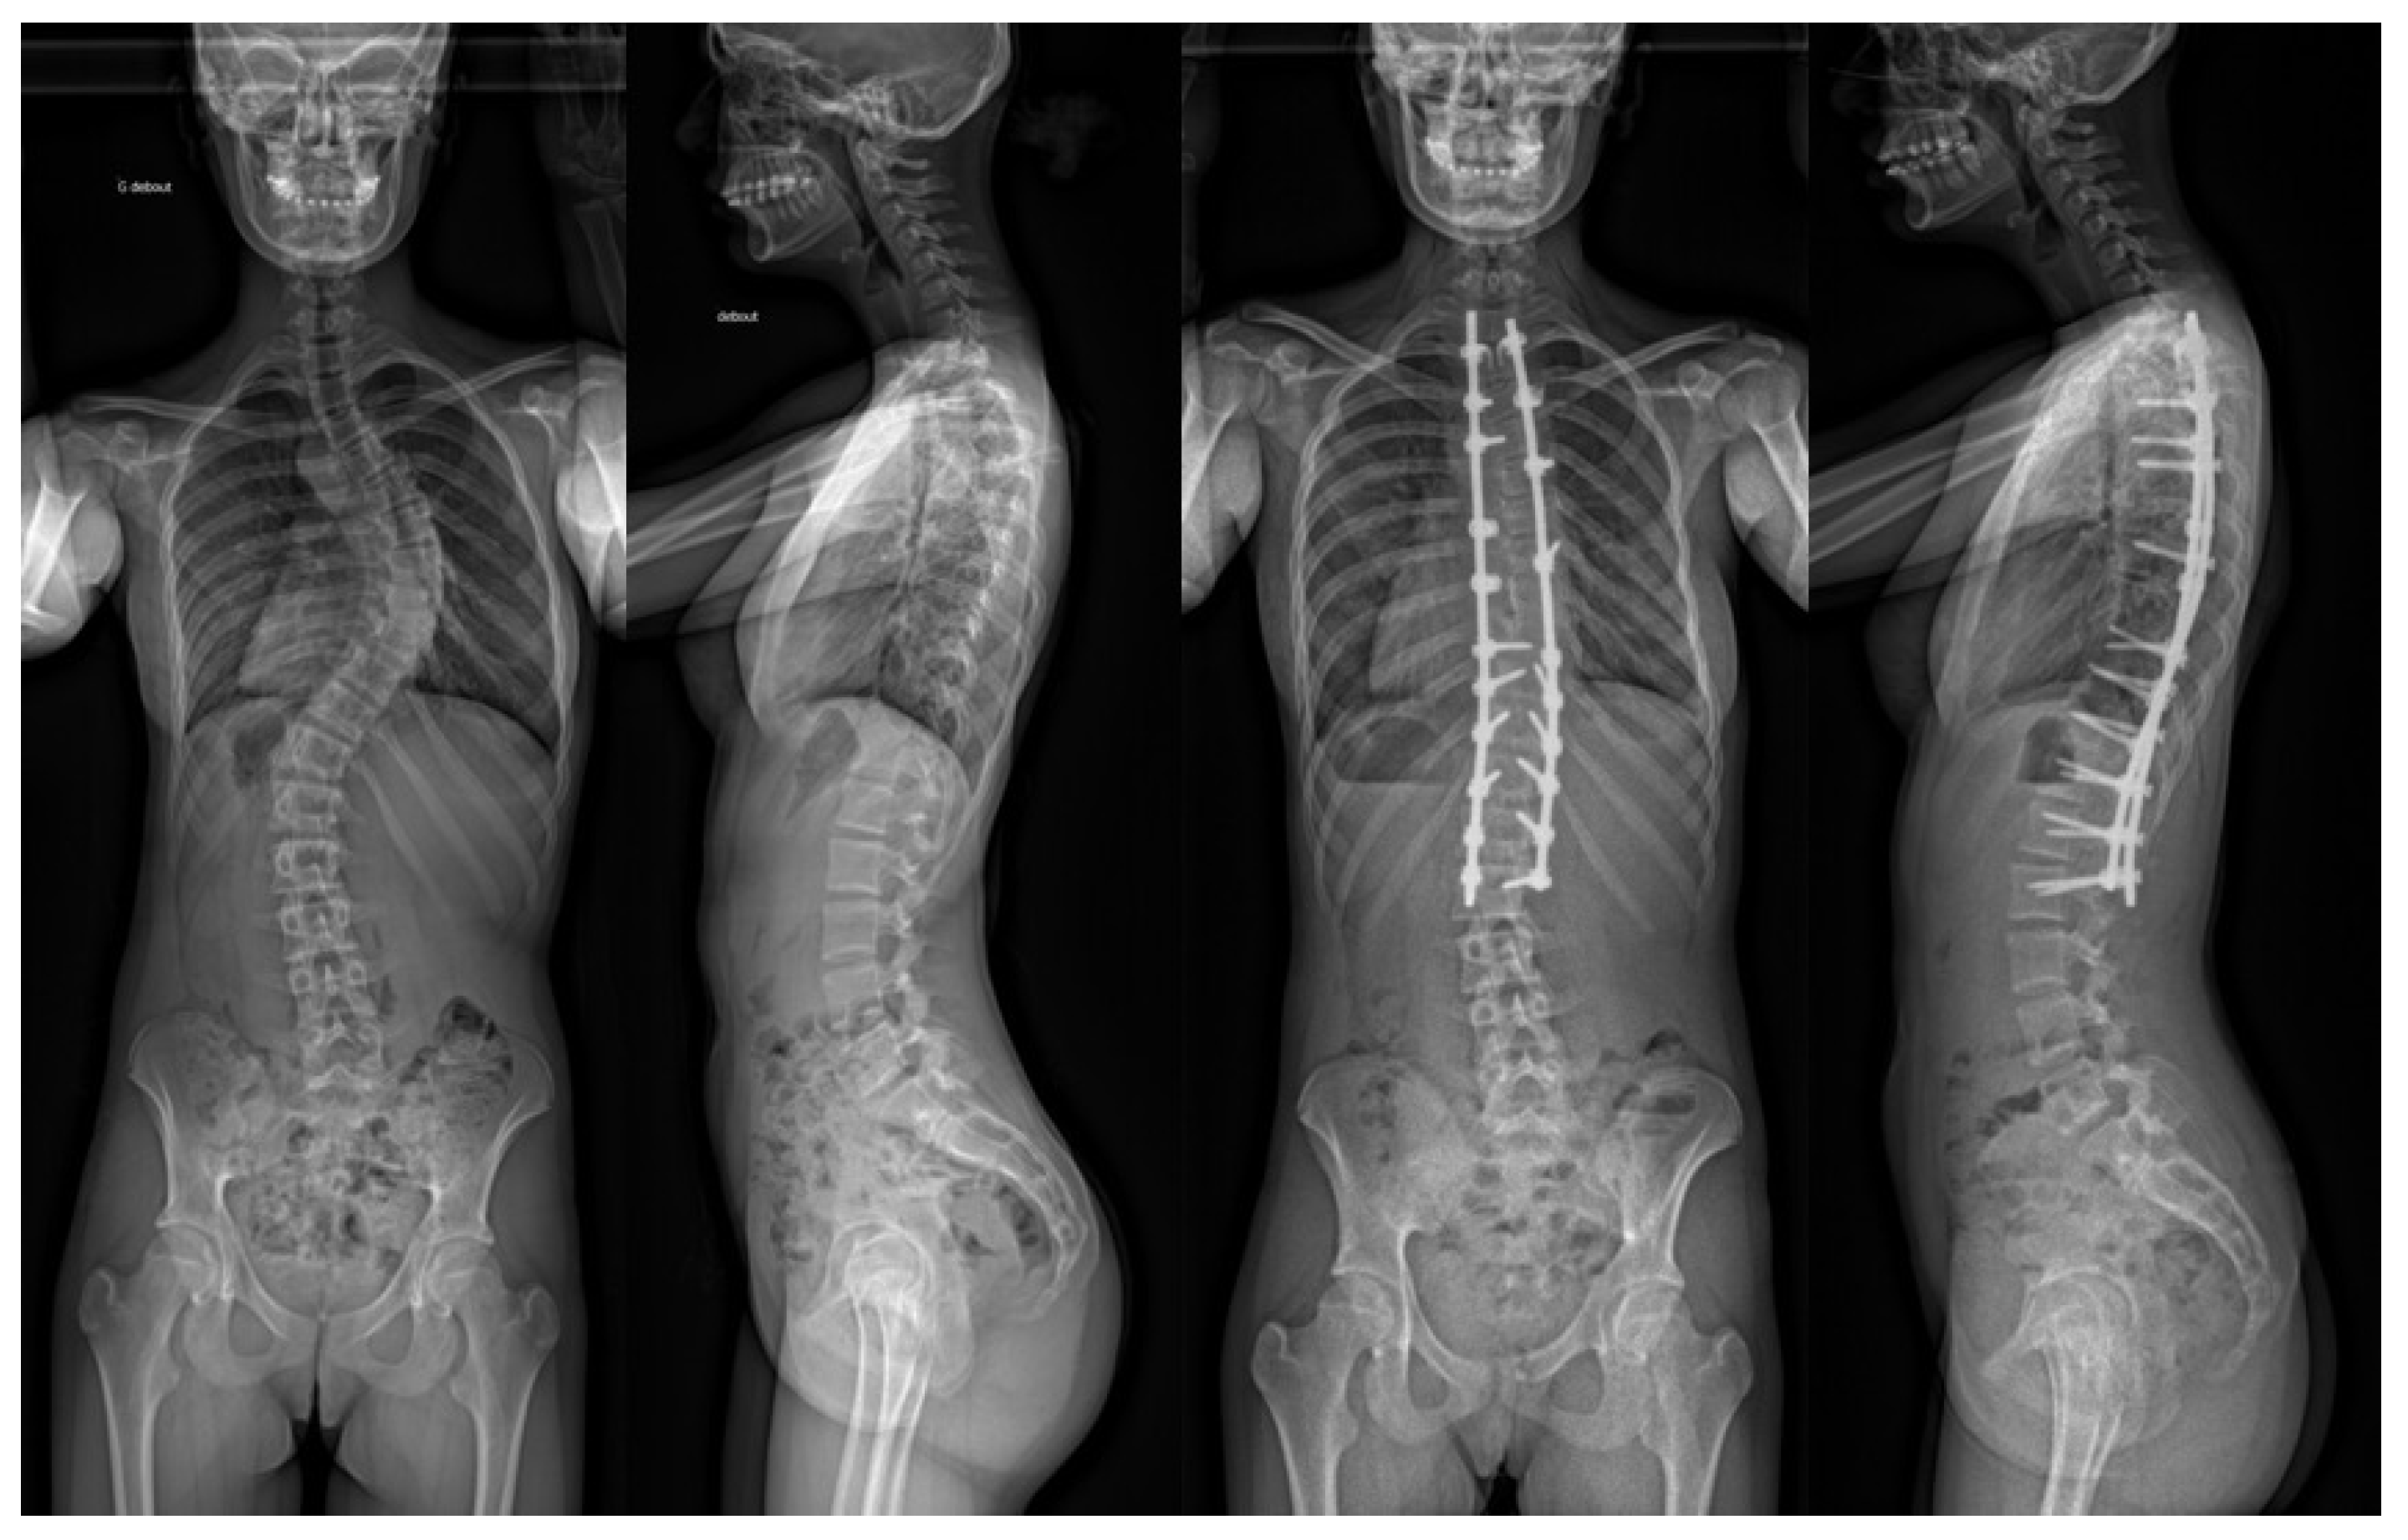

3.4. Radiographic Analysis

| Pre-op | 62.7 ± 22.7 (43) | [30–130] | / | 70.4 ± 24.9 (18) | [42–130] | / | 57.2 ± 19.6 (25) | [30–120] | / |

| 1st erect | 26.5 ± 16.4 (43) | [0–68] | p < 0.05 from pre-op (7.10−13) | 30.1 ± 17.9 (18) | [2–68] | p < 0.05 from pre-op (3.10−6) | 23.9 ± 15.1 (25) | [0–50] | p < 0.05 from pre-op (2.10−8) |

| 3–6 months | 24.0 ± 13.9 (25) | [0–50] | p < 0.05 from pre-op (8.10−11) | 23.0 ± 7.1 (2) | [18–28] | p < 0.05 from pre-op (0.02) | 24.1 ± 14.5 (23) | [0–50] | p < 0.05 from pre-op (3.10−8) |

| 24 months | 27.1 ± 16.1 (42) | [0–70] | p < 0.05 from pre-op (10−12) | 31.2 ± 18.6 (17) | [7–70] | p < 0.05 from pre-op (9.10−6) | 24.1 ± 14.1 (25) | [0–52] | p < 0.05 from pre-op (10−8) |

| Correction rate | |||||||||

| Pre-op vs. 1st erect (°) | 36.2 ± 12.0 (43) | [15–70] | / | 40.3 ± 11.4 (18) | [24–70] | / | 33.2 ± 11.7 (25) | [15–70] | / |

| Loss of correction | |||||||||

| 1st erect vs. 3/6 months (°) | −0.55 ± 3.32 (25) | [−8.0–5.0] | p = 0.874—NS | 0.00 ± 5.7 (2) | [−4.0–4.0] | p = 0.950—NS | −0.60 ± 3.25 (23) | [−8.0–5.0] | p = 0.773—NS |

| 1st erect vs. 24 months (°) | −0.65 ± 3.24 (42) | [−7.0–7.0] | p = 0.671—NS | −1.12 ± 3.52 (17) | [−7.0–7.0] | p = 0.685—NS | −0.18 ± 2.97 (25) | [−6.5–6.0] | p = 0.868—NS |